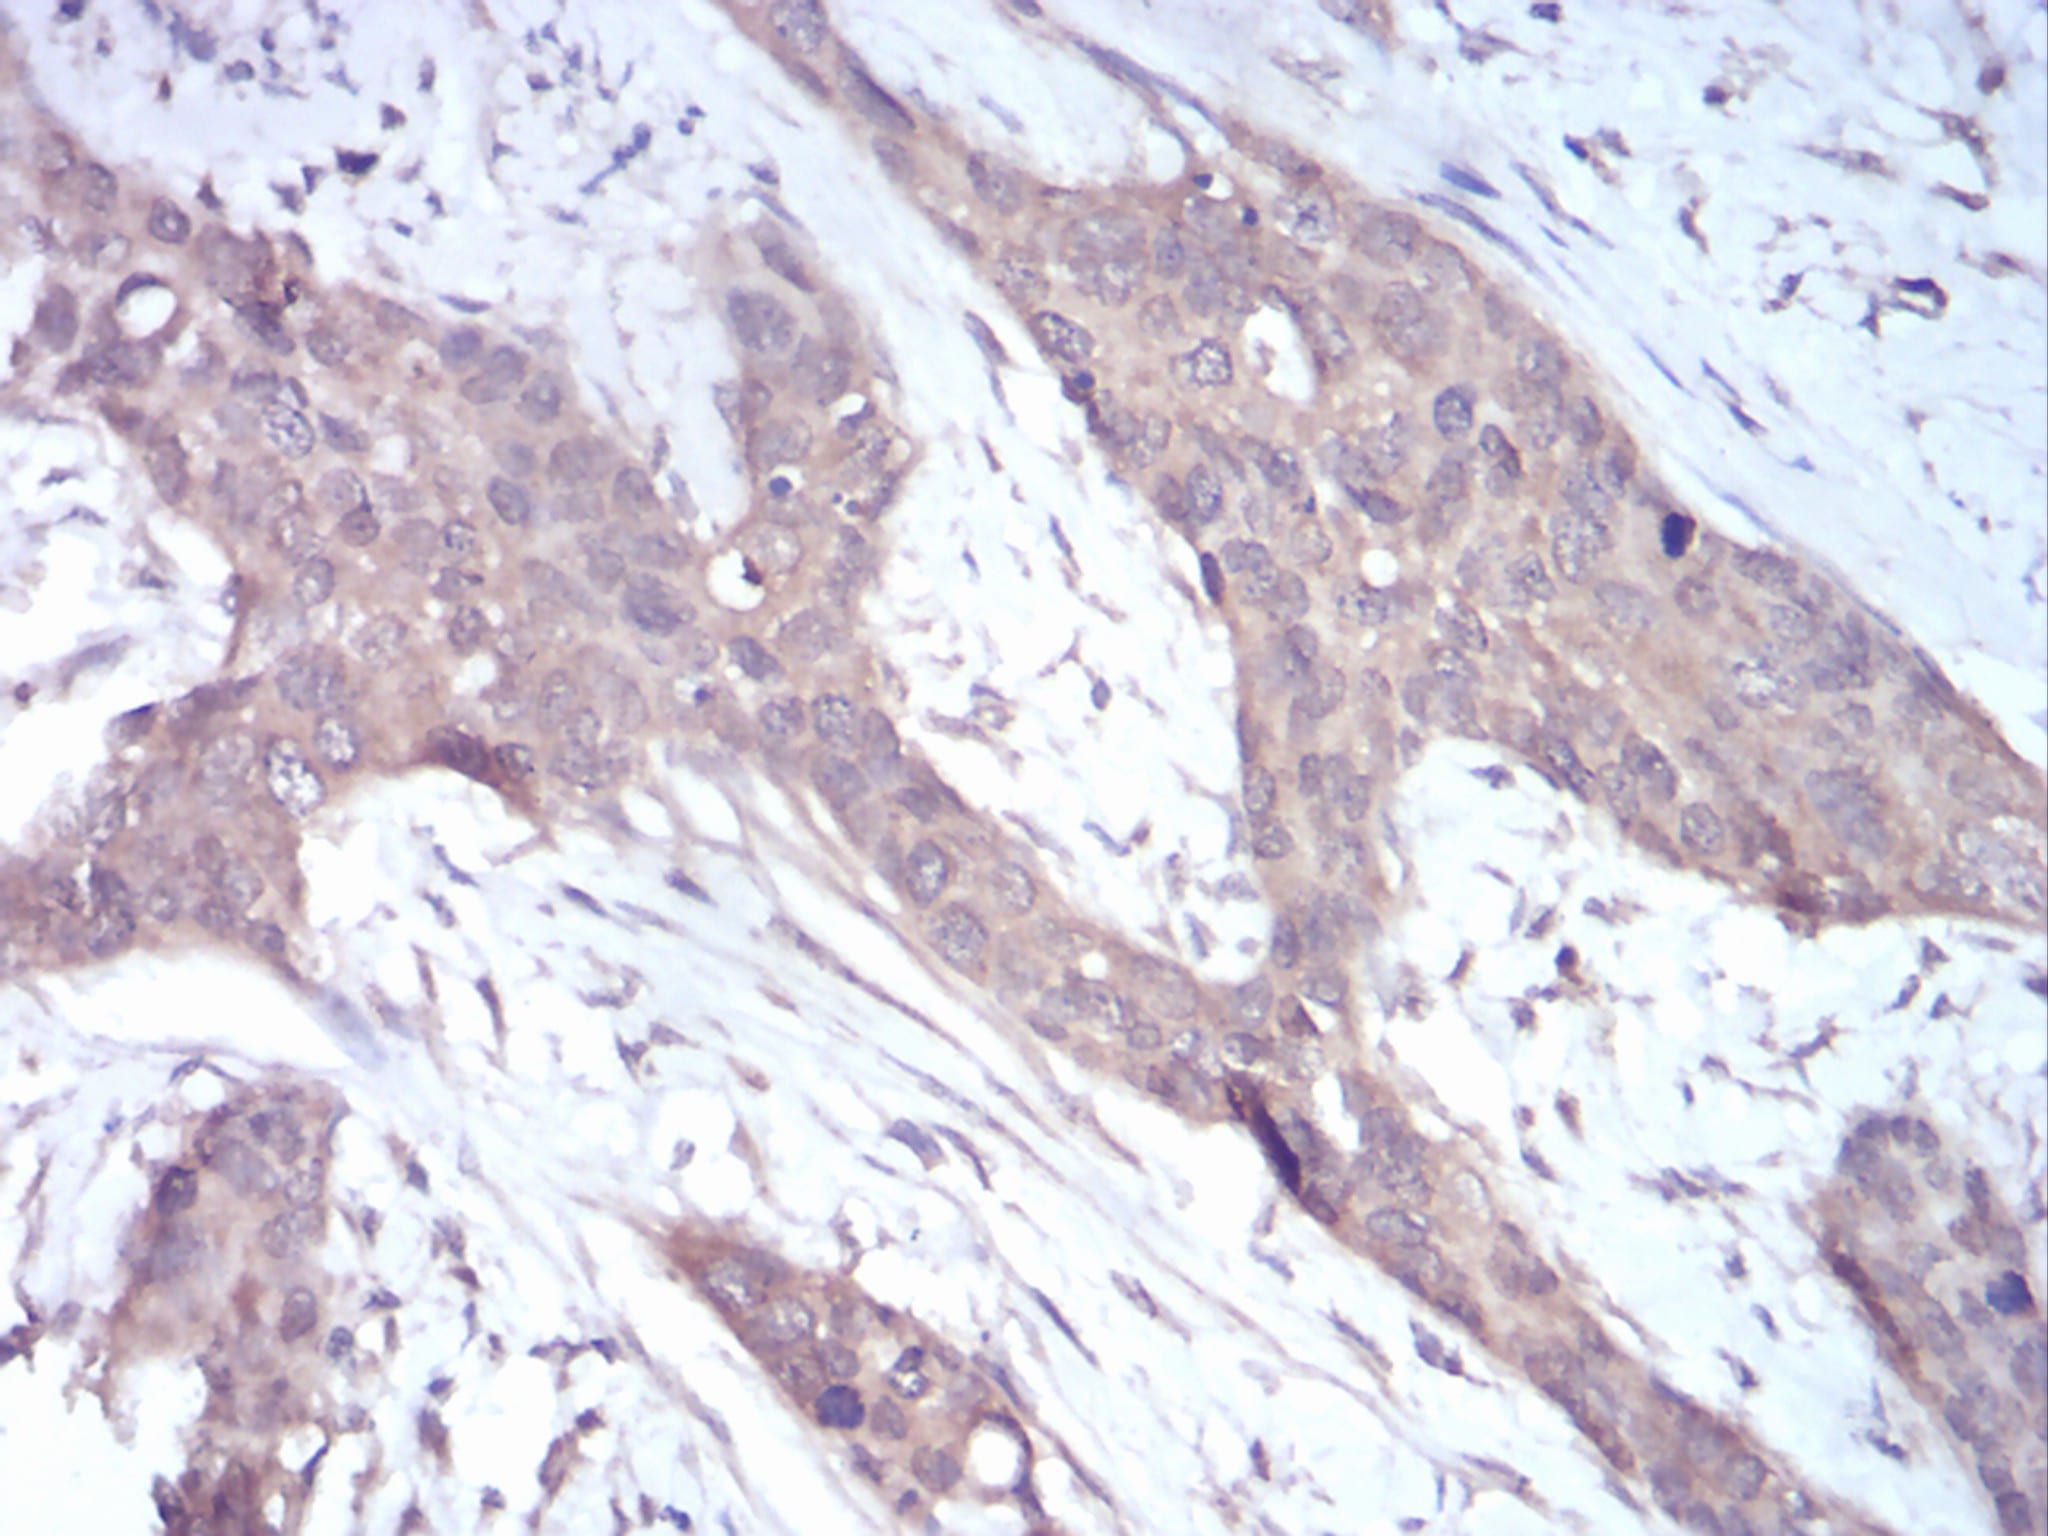

分类: 科研抗体货号: 30747别名: JTK10; THCYT3应用: IHC,FCM反应种属: Human

分类: 科研抗体货号: 30755别名: HER4; ALS19; p180erbB4应用: IHC,FCM反应种属: Human

分类: 科研抗体货号: 30754别名: KOX; KOX-1; RENOX应用: IHC,IF,FCM反应种属: Human

分类: 科研抗体货号: 30744别名: EIF-5A; EIF5A1; eIF5AI应用: IHC,FCM反应种属: Human